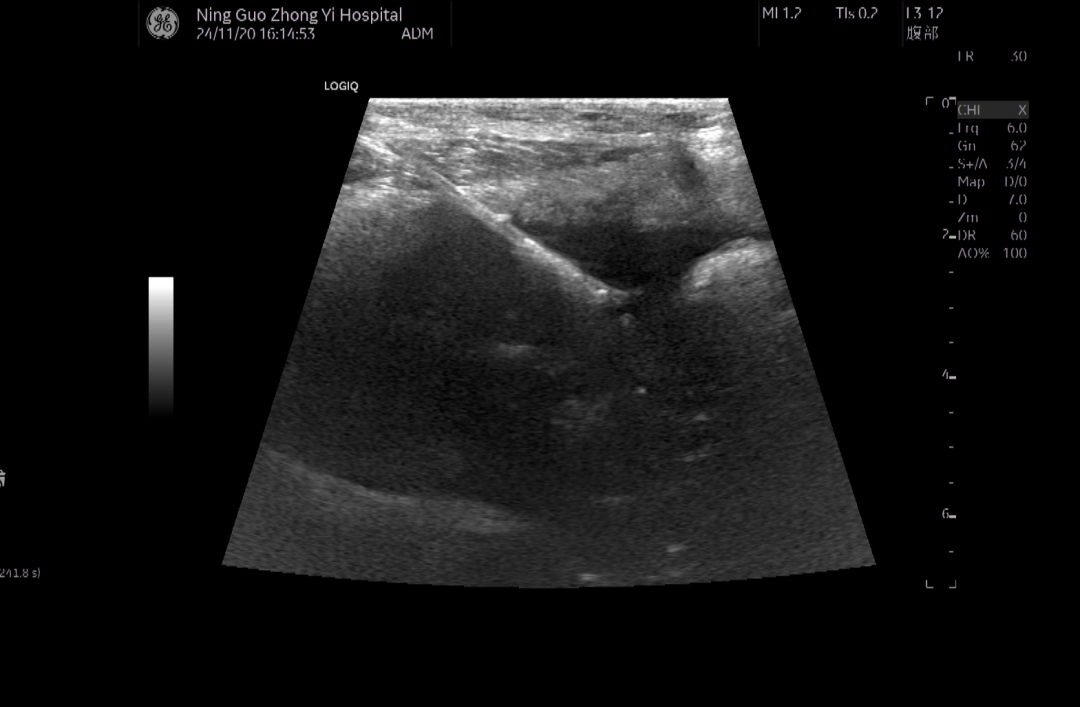

近期我院超声科迎来一例怀疑肠道肿瘤肝转移的患者,为明确病理,行腹腔内肠道周边肿块穿刺活检,经一番穿刺术前检查后,在超声实时监视引导下经皮经腹腔,穿刺针精准到达肿块边缘,击发成功,取得满意组织条,术中无明显出血,术后加压包扎,密切观测生命体征,无并发症。病理报告腺癌,明确了诊断,为下一步治疗指明方向。 近期超声科也遇到一例外周肺实变的患者,为明确病理,行实变肺组织穿刺活检,经一番穿刺术前检查后,在超声实时监视引导下经皮经胸腔,穿刺针精准到达实变肺组织内,击发成功,取得满意组织条,术中无明显出血,术后密切观测生命体征,无并发症。病理报告显示实变肺组织为炎性组织,明确了诊断,确定了治疗方向,取得满意效果。去年超声科对一位周围型肺肿块患者也在超声实时监视引导下经皮经胸腔行肿块穿刺活检,做了病理和免疫组化检测,明确诊断为肺腺癌,为治疗方案提高了依据。 我院超声科超声介入从过去的甲状腺、乳腺结节以及浅表淋巴结穿刺活检到如今的胸腹腔脏器肿块的穿刺活检是一个技术不断进步不断成熟发展的飞跃。超声科将不断提升实力,精准高效的服务好病患。 |